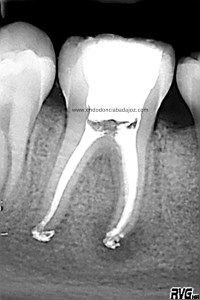

Bueno, pues hoy voy a poner un casito de otro molar inferior, un 4.6, de un chico de unos 14 años. Presentaba una necrosis con una lesión periodontal

Cuando tratamos a niños, tenemos que entender que en muchas ocasiones los conductos no se han cerrado formando sistemas de conductos muy difíciles de limpiar tanto química como mecánicamente. Es este caso, presentaba un istmo mesial acintado que lo tratamos como si tuviese varios conductos. Colocamos H de Ca, soy ,en ciertos casos, un defensor del medicamento intraconductos, con lo que lo hicimos en  dos sesiones.

Una vez que hemos limpiado los conductos con un sistema de instrumentación  Protaper en combinación con limas K3. Pasamos a obturar los mismos con una técnica de condensación vertical de ola contínua de Buchanan y un backfilling con la gutapercha inyectada de la pistola ObturaII. Tomamos varias proyecciones, orto-mesio-distal

Con estas tres proyecciones nos quedamos mucho más tranquilos y seguros de un buen sellado hermético y tridimensional des sistema de conductos de esta pieza.

Llamamos a revisión 9 meses después a nuestro paciente: